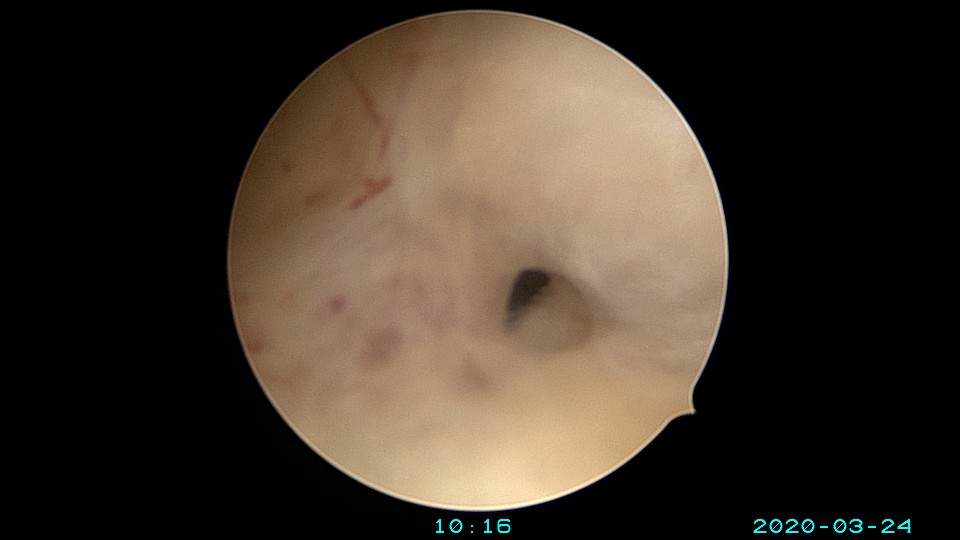

患者65岁,G1P1,顺产1次。安环30年,绝经10年。外阴白斑,阴道明显萎缩,无法置入扩阴器,阴道内镜方式找到宫颈外口,宫颈萎缩,穹隆几乎消失,无法夹持宫颈,宫颈管见多个息肉,宫颈内口狭窄坚硬,难以扩张。微型异物钳探查宫腔方向,用异物钳、微型剪刀扩大宫颈内口失败,改用双极电针切开宫颈内口,但镜子仍无法进入宫腔。用异物钳反复牵拉O型环至阴道内,中弯钳配合卵圆钳拉出节育环,环变形。有人问我何不用取环钩取环,这个病人探针和取环钩都无法发挥作用。